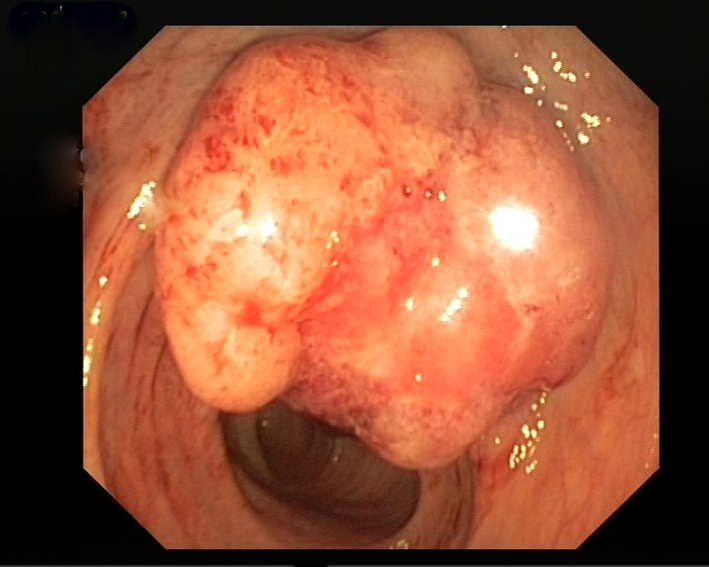

A 60-year-old female patient, with a history of cholecystectomy approximately 1 month ago and a history of using high-dose analgesics due to low back pain, has applied to the emergency service of our hospital with the complaint of rectal bleeding lasting for a week and due to general condition disorder. It has been indicated that routine tests performed at the control visit of the patient approximately 2 weeks ago were normal. In the initial tests performed at the emergency service, the following results were found: WBC: 8.6 × 109/L, Hb: 8.52 g/dL, PLT: 22 × 109/L, AST: 64 U/L, ALT: 46 U/L, LDH: 850 U/L, T. bil: 1.88 mg/dL and D. Bil: 0.79 mg/dL. Patient has been admitted to the hematology clinic with the pre-diagnosis of acute leukemia. In peripheral smear examination, no atypical cell has been observed. In abdominal ultrasonography, no pathology has been observed. Bone marrow aspiration biopsy performed has resulted as dry tap. In bone marrow imprint examination, it has been determined that cells with atypical nucleoli were compliant with distant organ metastasis causing syncytium. In bone morrow biopsy examination, there were atypic looking mucin islets and tumor cell groups occupying bone marrow spaces, among calcific bone spicules (Fig. 1). No pathology has been observed in upper endoscopic examination; in colonoscopy examination performed thereupon a massive lesion of 14 to 18 cm has been detected at rectum (Fig. 2). Mass biopsy has been observed to be consistent with rectal carcinoma. Patient, considered to have bone marrow infiltration of rectal carcinoma, has been referred to the oncology clinic for the organization of her treatment.

![]() Click for large image | Figure 2. Colonoscopy examination. Performed thereupon a massive lesion has been detected at rectum. |